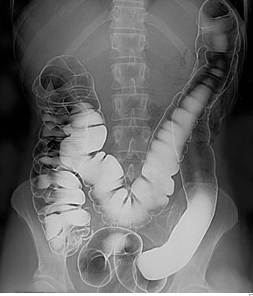

大腸鋇劑灌腸造影是X 光的一種。檢查時,醫護人員會把鋇劑灌入肛門,鋇劑會經直腸進入結腸。在X光下,進行實時檢測,可以檢視出大腸內阻塞、結節以及腫瘤等等。

檢查前,病人需要盡量進食流質食物,及避免含高纖維食物,也需要服用依指示服用瀉藥,才進行灌腸清洗程序。灌腸造影檢查可能會引起患者腹痛不適。病人如最近曾經進行手術,腸壁可能會有輕微破損,會導致大腸穿孔,而導致嚴重併發症。